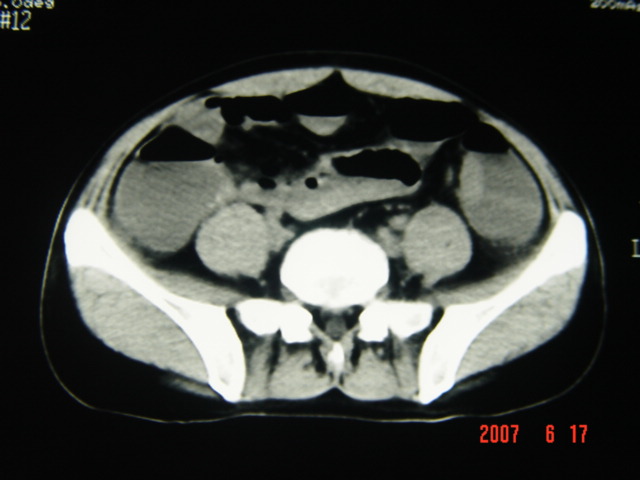

[br][br]以下是引用lkc8963在2007-6-17 13:32:00的发言:[br]完全支持邓主任意见:降/乙交界部占位性病变伴不全梗阻.做个增强或者be可能更好.